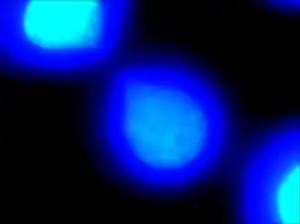

| DAPI staining allows for visualization of deoxyribonucleic acid portions of the two daughter cells. The thin “string-like” DNA connecting them is defined as a chromatin bridge. | |

Chromatin bridges are easiest and most readily visible when observing chromosomes stained with DAPI. DNA bridges appear to be a blue, “string-like” connection between two separated daughter cells. This effect is created when sticky ends of chromosomes remain connected to one another, even after mitosis. A chromatin bridge may also be observed using indirect immunofluorescence, in which anti-tubulin emits a green coloration when bound to microtubules in the presence of UV light. Because microtubules maintain the positions of the chromosomes during mitosis, they appear to be densely pinched between the two dividing, daughter cells. Chromatin bridges can be difficult to locate utilizing fluorescence microscopy, as this phenomenon is not incredibly abundant and tend to appear faint against the dark background.